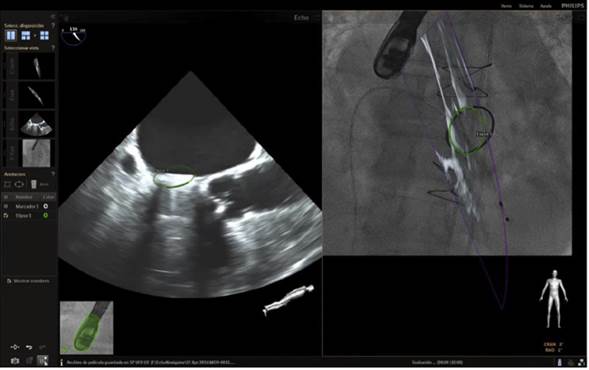

En la actualidad, la implantación de Mitraclip se acepta como una alternativa en el tratamiento de la insuficiencia mitral para pacientes con alto riesgo quirúrgico23. Los pasos críticos en el éxito del procedimiento son la punción transeptal y la colocación del Mitraclip. La ecocardiografía 2D/3D es la modalidad de elección durante el procedimiento. Previamente se mencionó la técnica empleada en la punción septal; en cuanto a su utilidad como guía (fig. 11), la fusión de imagen desempeña un papel fundamental en la trayectoria inicial del clip en la entrada a la aurícula y luego su orientación en el objetivo de alcanzar una posición ideal en la válvula mitral (figs. 12-15).

Figura 12 Imagen de fusión. Procedimiento de colocación de Mitraclip. Paso de clip a través del catéter e inicio de maniobra de giro hacia la válvula mitral.

Figura 13 Imagen de fusión. Procedimiento de colocación de Mitraclip. Clip que gira dentro de la aurícula izquierda buscando ángulo de 90( respecto a la válvula mitral.